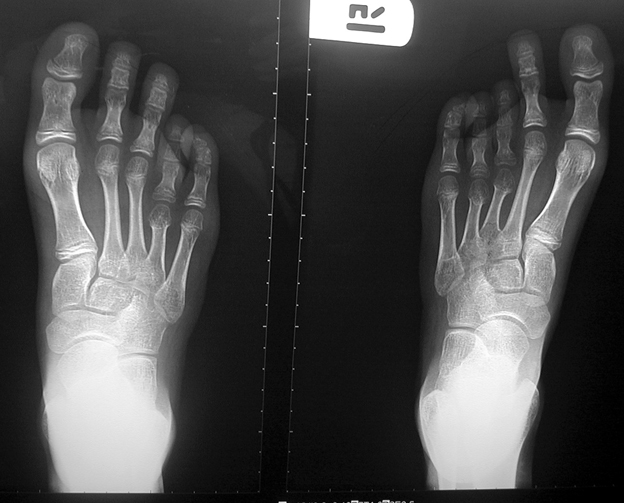

El parmağı (metakarp) ve ayak parmağı (metatars) kısalıkları doğuştan tek başına, geniş bir sendrom grubuyla birlikte, travma sonrası, Freiberg hastalığı (avasküler nekroz) sonrası görülebilir.

Doğuştan metakarp ve metatars kısalığının görülme sıklığı 1/1000’den azdır. Kadınlarda erkeklere göre 5 kat daha fazla görülür ve sıklıkla (%72) iki taraflıdır. En sık 4. parmak tutulur. Bu tür olgularda sorunun nedeni tam olarak bilinmemekle brlikte deformitenin genellikle epifiz plağının erken kapanmasından kaynaklandığı düşünülmektedir.

Doğuştan metakarp ve metatars kısalıklarının redavisi için pek çok teknik tanımlanmakla birlikte en çok akut uzatma sonrası kemik uçlarına greft konması ve distraksiyon osteogenezi (kallotasis) kullanılmaktadır. 1 cm.den daha fazla uzatma gereken olgularda kallotasis yöntemi önerilmektedir. Kliniğimizde de metatars ve metakarp uzatma için unilateral eksternal fiksatör ve sirküler eksternal fiksatör yardımıyla distraksiyon osteogenezi yöntemi tercih edilmektedir.